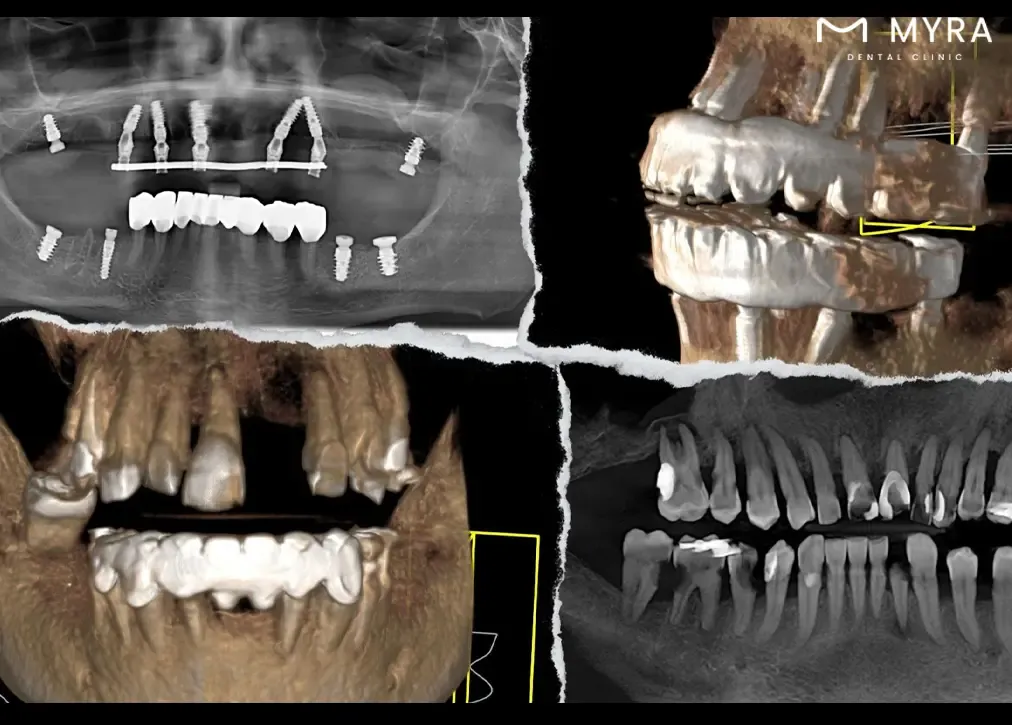

The role of Sirona 3D Dental Tomography in dental practises is to serve as the pinnacle device for advanced diagnosis and treatment in dental radiology. The technology’s significance lies in its ability to provide high-end images of the cranio-maxillofacial imaging area, offering a detailed map of the oral and dental structures. The device's Adaptive Focal Positioning (AFP) function ensures high clarity in imaging, allowing for precise analysis of multiple layers in exposures.

The Sirona 3D Dental Tomography is very useful because it combines different tomography layers into a single image that ensures all parts are visible, from the tooth's crown to the area between the teeth. The technology goes beyond traditional 2D X-rays, allowing for the viewing of hidden details that are crucial for diagnosis, treatment planning, and follow-up stages of oral and dental health.

The Sirona 3D Dental Tomography's capacity to generate precise 3D images that aid in the diagnosis of conditions such as buried teeth, abnormal canal numbers, fractures, and cyst spread further emphasises its role. Its benefits extend to providing better image quality and higher accuracy, offering clear views of bone and soft tissues with a low radiation dose, and ensuring a quick and painless solution for patients.

Adaptive Focal Positioning (AFP): AFP function ensures high clarity in imaging by analysing multiple layer exposures. It controls each region, selects optimal tomography layers, and transforms them into a new image. The adaptive nature of its function allows for customization based on specific diagnostic needs.

Rotational Scanning: The device rotates 180 degrees around the patient's head during the scanning process. The rotational scanning captures detailed images from different angles, contributing to the three-dimensional reconstruction.

Computer Software Processing: Advanced computer software processes the captured images, creating sections as thin as two-tenths of a millimetre. The sections are compiled to generate the final 3D images.

Volumetric Imaging: The device creates a volumetric image of the skull, allowing for a comprehensive examination of the bone structure. The three-dimensional view enhances the diagnostic capabilities of dental tomography.

Focused Image Reconstruction: The adaptive nature of the focal positioning function ensures that each element, from the apex of the tooth to the incisal region, is perfectly in focus. The focused reconstruction contributes to the clarity and accuracy of the images.

Conical Beam CT Technology: Sirona 3D Dental Tomography employs conical beam CT technology, which focuses X-rays at a specific point, enabling the imaging of small areas with high precision. The technology is a key part of getting more accurate diagnoses.

The Sirona 3D Dental Tomography procedure works on a principle that involves capturing full three-dimensional images of the maxillofacial and dental structures. The process utilises advanced imaging technology to provide comprehensive views of the teeth, jawbone, and surrounding tissues.

The procedure begins with the patient being positioned appropriately, usually with the jaw placed in the designated area of the imaging device. The Sirona 3D Dental Tomography device rotates around the patient's head, capturing multiple X-ray images from various angles. A precise and three-dimensional picture of the maxillofacial and oral structures is captured using the rotational movement.

Sirona 3D Dental Tomography allows dentists to gain a more in-depth understanding of dental and jaw-related issues. The three-dimensional images enable precise and accurate diagnoses of conditions such as tooth decay, buried or impacted teeth, fractures resulting from trauma, bone defects, and the periodic assessment of implants.

The procedure aids in treatment planning by offering a higher level of detail and accuracy. Dentists configure root canals, measure root canal dimensions, and conduct detailed assessments of bone density, sinuses, and joints. The technology helps in the planning of dental implant procedures, offering a three-dimensional evaluation of the jawbone structure.

The Sirona 3D Dental Tomography procedure is designed to contribute to higher treatment success rates by providing dentists with advanced diagnostic tools. Dental professionals are able to improve their diagnostic capabilities and create more effective and personalised treatment plans with the ability to provide detailed and precise images.